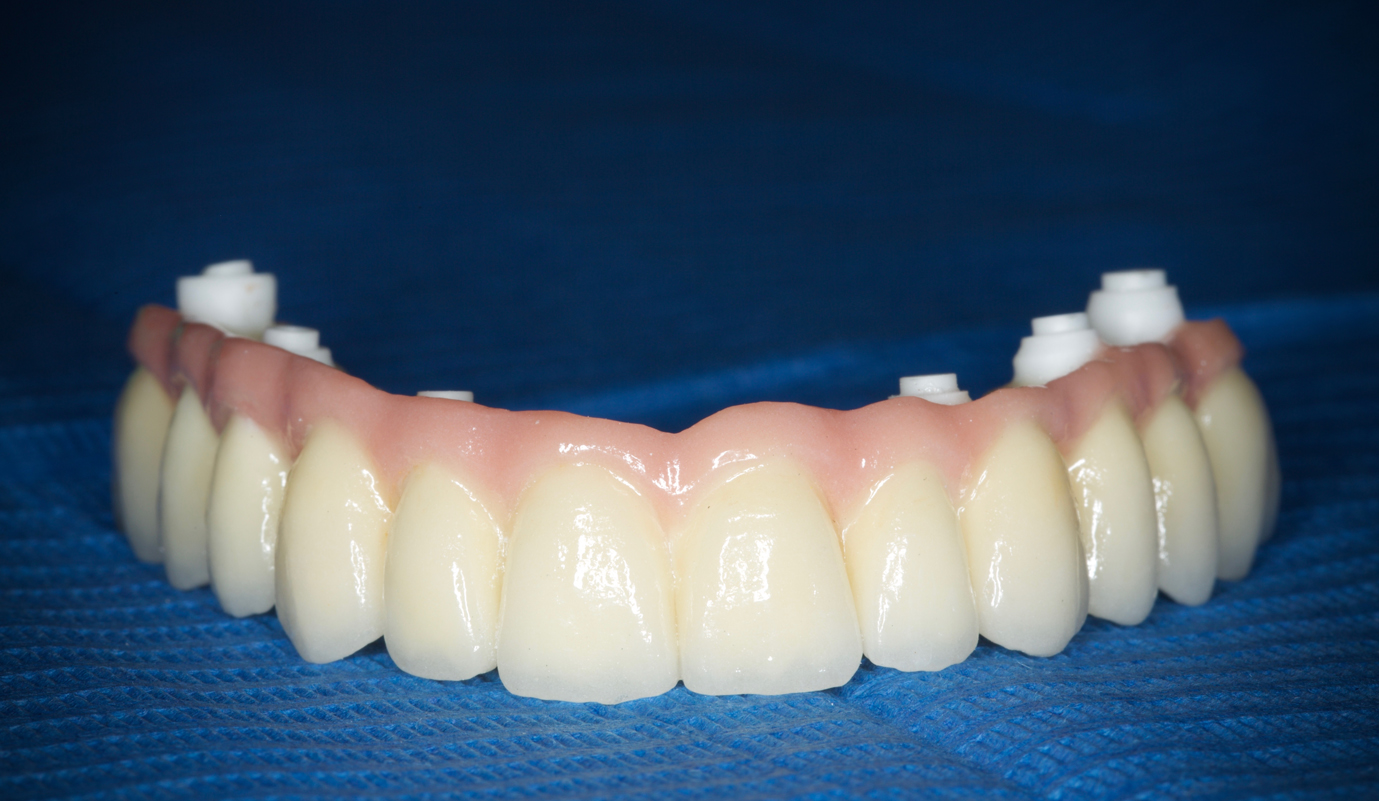

Sobre implantes as soluções podem ser para casos unitários ou múltiplos, com estruturas fixas para reabilitar arcadas totais. Estes funcionam como se fossem umas “raízes dentárias artificiais” onde são fixas as coroas cerâmicas. São soluções apetecíveis pelo facto de dar a sensação de ter novamente dentes, mas têm de ser mantidas com cuidado redobrado pois acabam por ser peças artificiais e o que pretendemos é que sejam definitivos sem que haja qualquer tipo de problema posterior.

Exemplos em fase laboratorial

Casos de próteses sobre implantes